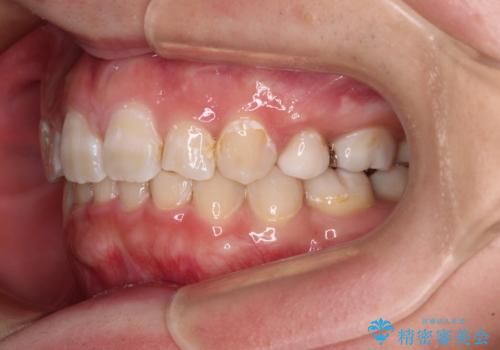

著しい八重歯を短期間で改善 ワイヤー装置による抜歯矯正

- 八重歯と下顎小臼歯の欠損を気にして来院された患者様です。

下顎小臼歯の欠損により過蓋咬合となっていたため、下顎は臼歯を起こすことで咬み合わせを改善し、八重歯は第一小臼歯2本を抜歯し、補助装置を使用して速やかに改善することとしました。

著しい過蓋咬合の改善が必要であった割には、治療期間は2年強と標準的でした。

八重歯は3,4か月で速やかに改善されました。